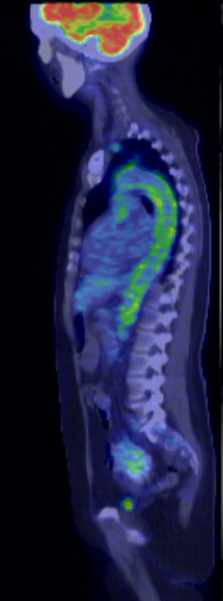

21.4.1.3.2. Somatostatin receptor scintigraphy

Many tumors express somatostatin receptors, especially the various types of neuroendocrine tumors (for example carcinoid, meningeoma, medulloblastoma and neuroblastoma). These can be investigated with somatostatin analogue peptides, most commonly with pentetreotide, an 111In isotope labeled peptide (OctreoScan). This examination is primarily significant in carcinoid and GEP (gastroenteropancreatic) tumor (gastrinoma, insulinoma, glucagonoma, VIPoma) diagnostics. Although GEP tumors present with a severe clinical picture, they are usually small and their detection with other imaging modalities is difficult. For this reason, somatostatin receptor scintigraphy is the recommended method of first choice. If the carcinoid is well differentiated, it is able to detect the lesion and possible metastases. Furthermore, it is useful in therapy monitoring and in cases of planned liver transplantation to rule out extrahepatic metastases. (Figure 13.)

Image

a

b

c

13. Somatostatin receptor scintigraphy (Octreoscan). Planar anterior (a), transversal (b) and coronal (c) fusion SPECT-CT images. Multiplex liver metastases, the primary neuroendocrine tumor is in the head of the pancreas.